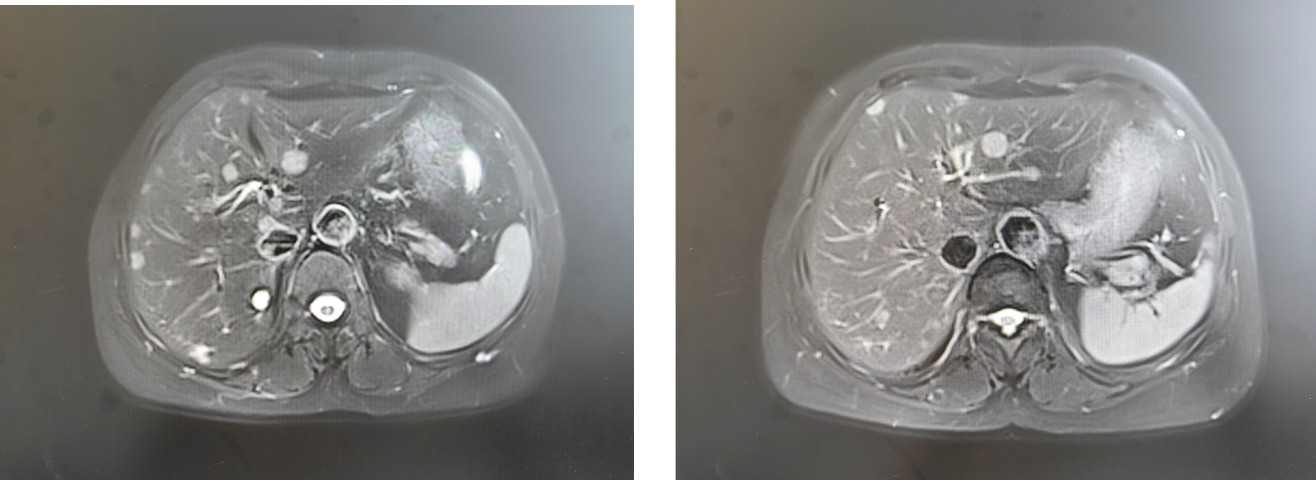

用药2个月后(2025年9月4日)复查肝脏磁共振,病灶较基线(2025年6月25日)明显缩小,疗效评估为PR 。

5.png